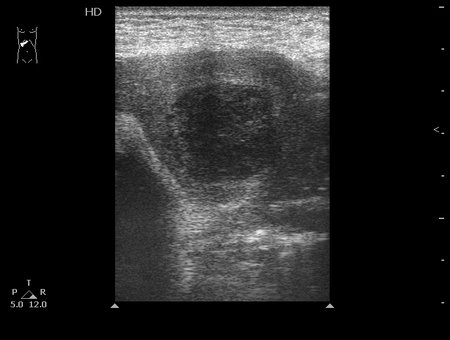

#2

10-04-09-145915_2903_201004.jpg

Типичная картина ##1-4:

Гипоэхогенное неоднородное округлое образование, окруженное эхогенным "демаркационным валом"

измененной паренхимы печени.